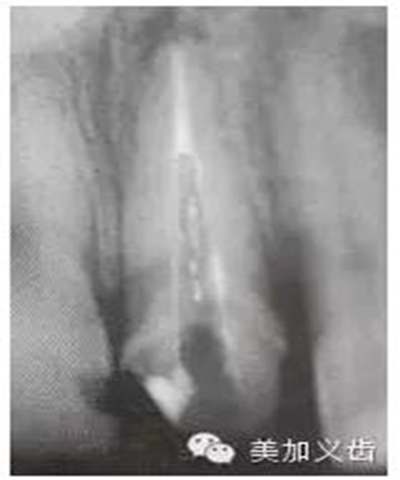

預(yù)備后根管壁上會(huì)不同程度的牙膠和封閉劑等殘留物,所以樁道預(yù)備前后建議X線片輔助檢查預(yù)備深度等情況,而殘留物也會(huì)很清晰地顯現(xiàn)。